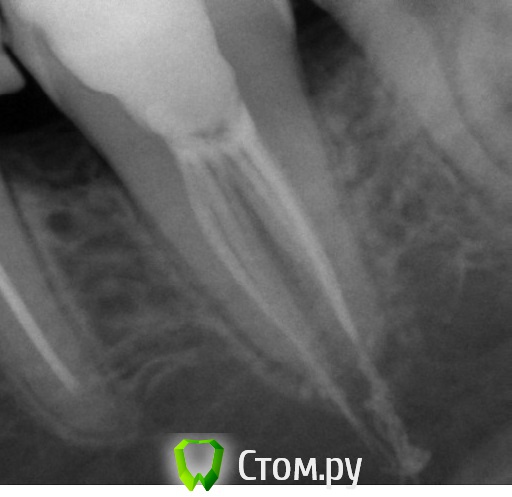

Анастасия Неклюдова Опубликовано 20 декабря, 2013 Поделиться Опубликовано 20 декабря, 2013 (изменено) 5 дней назад запломбировали каналы нижней 7ки. После того, как отошел наркоз, постоянная ноющая боль. Накусывать не больно. Врач уехала в отпуск до 29го декабря. сегодня сделала снимок в клинике по соседству. Прокомментируйте, пожалуйста. Заранее благодарю. Изменено 20 декабря, 2013 пользователем Анастасия Неклюдова Ссылка на комментарий

IvanK Опубликовано 20 декабря, 2013 Поделиться Опубликовано 20 декабря, 2013 Здравствуйте,есть выход пломбировочного материала за пределы корня. болезненность после пломбировки может быть если боль не утихает: перелечить , при не благоприятном течении - удалить. Ссылка на комментарий

red_butler Опубликовано 20 декабря, 2013 Поделиться Опубликовано 20 декабря, 2013 (изменено) Сделайте панорамный снимок. За верхушки корней выведен пломбировочный материал. Если боли не пройдут, может потребоваться операция по его удалению.А снимки до, во время, и после лечения Вам не делали? Изменено 20 декабря, 2013 пользователем red_butler 1 Ссылка на комментарий

Анастасия Неклюдова Опубликовано 21 декабря, 2013 Автор Поделиться Опубликовано 21 декабря, 2013 Сделайте панорамный снимок. За верхушки корней выведен пломбировочный материал. Если боли не пройдут, может потребоваться операция по его удалению.А снимки до, во время, и после лечения Вам не делали?Нет, пользовались панорамным снимком 4х месячной давности. а есть какие-то терапевтические способы устранения боли? тепло/полоскание? Ссылка на комментарий